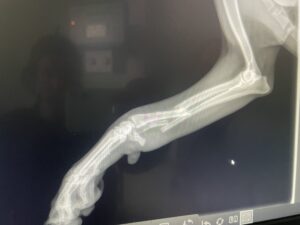

Sierra’s broken leg